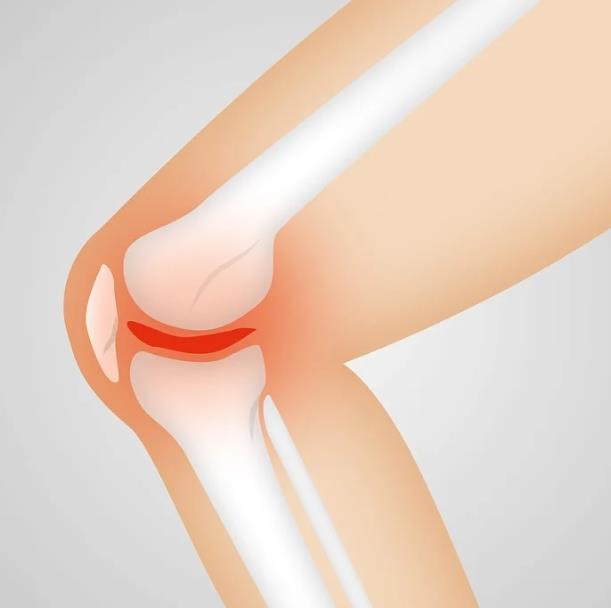

1. 퇴행성 관절염

병원을 찾는 환자들 중에 약 10~15%는 퇴행성관절염을 진단 받는다고 하는데요, 관절을 감싸고 있는 연골이 나이가 들어감에 따라 노화하거나 혹은 너무 많은 사용으로 손실이 생겨 발생하는 질환이라고 생각하면 됩니다.

평소 앉았다 일어날 때, 또 계단을 오를 때, 도보를 걸을 때 드드득, 혹은 드르륵 하면서 마치 뼈가 갈리는 듯한 소리가 난다면 퇴행성 관절염을 우선적으로 의심해봐야 합니다. 퇴행성 관절염에는 다리가 무겁게 느껴지거나, 무릎 아랫쪽 다리를 올리기 힘들다거나, 무릎 뒤쪽편이 당기는 증상도 있으니 참고하시면 좋을거 같습니다.

노화로 인해 생기는 경우가 많긴 하지만, 무릎쪽에 너무 무리를 줄 수 있는 과체중, 비만. 또 운동선수 같이 높은 강도의 훈련으로 인한 충격으로도 발생할 수 있기 때문에 꼭 나이 때문이라고 볼 수는 없습니다.

2. 추벽증후군

무릎이 딱딱 거리는 소리, 또 뼈가 갈리는거 같은 소리가 난다면 추벽증후군도 의심해볼 수 있습니다.

추벽증후군은 대퇴곤, 슬개골이 압박을 받거나 무리한 슬관절 사용, 외상을 당했을 때 많이 발생한다고 하며, 추벽의 두께가 점점 두꺼워 지면서 발생하는 증상 입니다. 탄발음, 종창, 무릎의 전방 통증 등이 나타나며 보통 MRI로도 어렵지 않게 증상 유무를 확인할 수 있습니다.

계단을 오를때 간헐적으로 앞쪽 슬관절 통증이 점점 잦아지거나, 탄발음, 딸깍거림 등이 느껴진다면 검사를 받는게 좋습니다.

3. 연골 연화증

무릎 관절에는 연골이 있는데, 이 연골이 약해지면서 발생하게 됩니다.

일반적으로 남성보다 여성에게 더 많이 발생하는 경향을 보이는데, 무릎 연골에 외상, 충격이 있을 때 발생하는 경우가 많습니다. 꼭 어디에 부딪혀서가 아니라도 무리한 다이어트를 하다가 연골 연화증이 생기거나, 심해지는 사례도 많이 있다고 합니다. 또 하이힐 등 굽이 높은 신발을 장시간 신고 활동하게 되면 슬개골에 무리를 주거나 손생되면서 생기는 경우도 있습니다.

무릎에서 뚝뚝 소리가 나요, 또 삭삭, 사각사각 비슷한 소리가 난다는 환자가 많으며, 무릎 앞쪽으로 통증이 느껴지거나 계단을 오르 내릴때, 무릎을 꿇을때, 쪼그릴 때 통증이 심하다면 의심해 보세요.